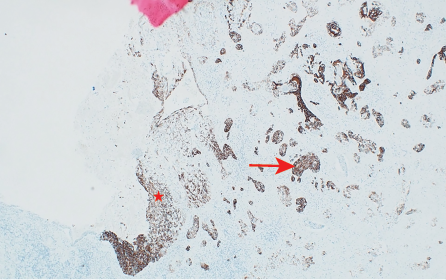

Histopathology showed a moderately-to-poorly differentiated 8 × 6 cm squamous cell carcinoma arising from the right kidney. The tumor cells showed a diffuse pattern and exhibited strong positivity for cytokeratin (CK) markers CK14 and CK5/6, in addition to the p63 marker. The tumor cells were negative for GATA3, uroplakin, RCC, and PAX8, and the associated squamous metaplastic lining of the renal pelvicalyceal system exhibited dysplasia highlighted by strong positivity for CK5/6, p63, and CK14, and negativity for uroplakin and GATA3 [Figures 2–4]. the pathological stage was pT4Nx. CT scans were performed at the last follow-up, nine months after surgery, and showed no evidence of disease recurrence. Cystoscopy did not show any tumor in the bladder, and the barbotage to the right ureter sent for cytology was negative for malignant cells. During the patient's last visit to the urology clinic, he was in good health and asymptomatic. A CT scan is scheduled for his next follow-up.

Figure 3: (Case 1) Photomicrograph showing p63 and CK5/6 immunohistochemical stains in dysplastic squamous mucosa (star) and in the invasive tumor (arrow) hematoxylin and eosin stain, magnification = 500 ×.

Figure 4: (Case 1) Photomicrograph showing CK14 immunohistochemical stain positive in dysplastic mucosa (star) and in the invasive carcinoma (arrow) hematoxylin and eosin stain, magnification = 100 ×.